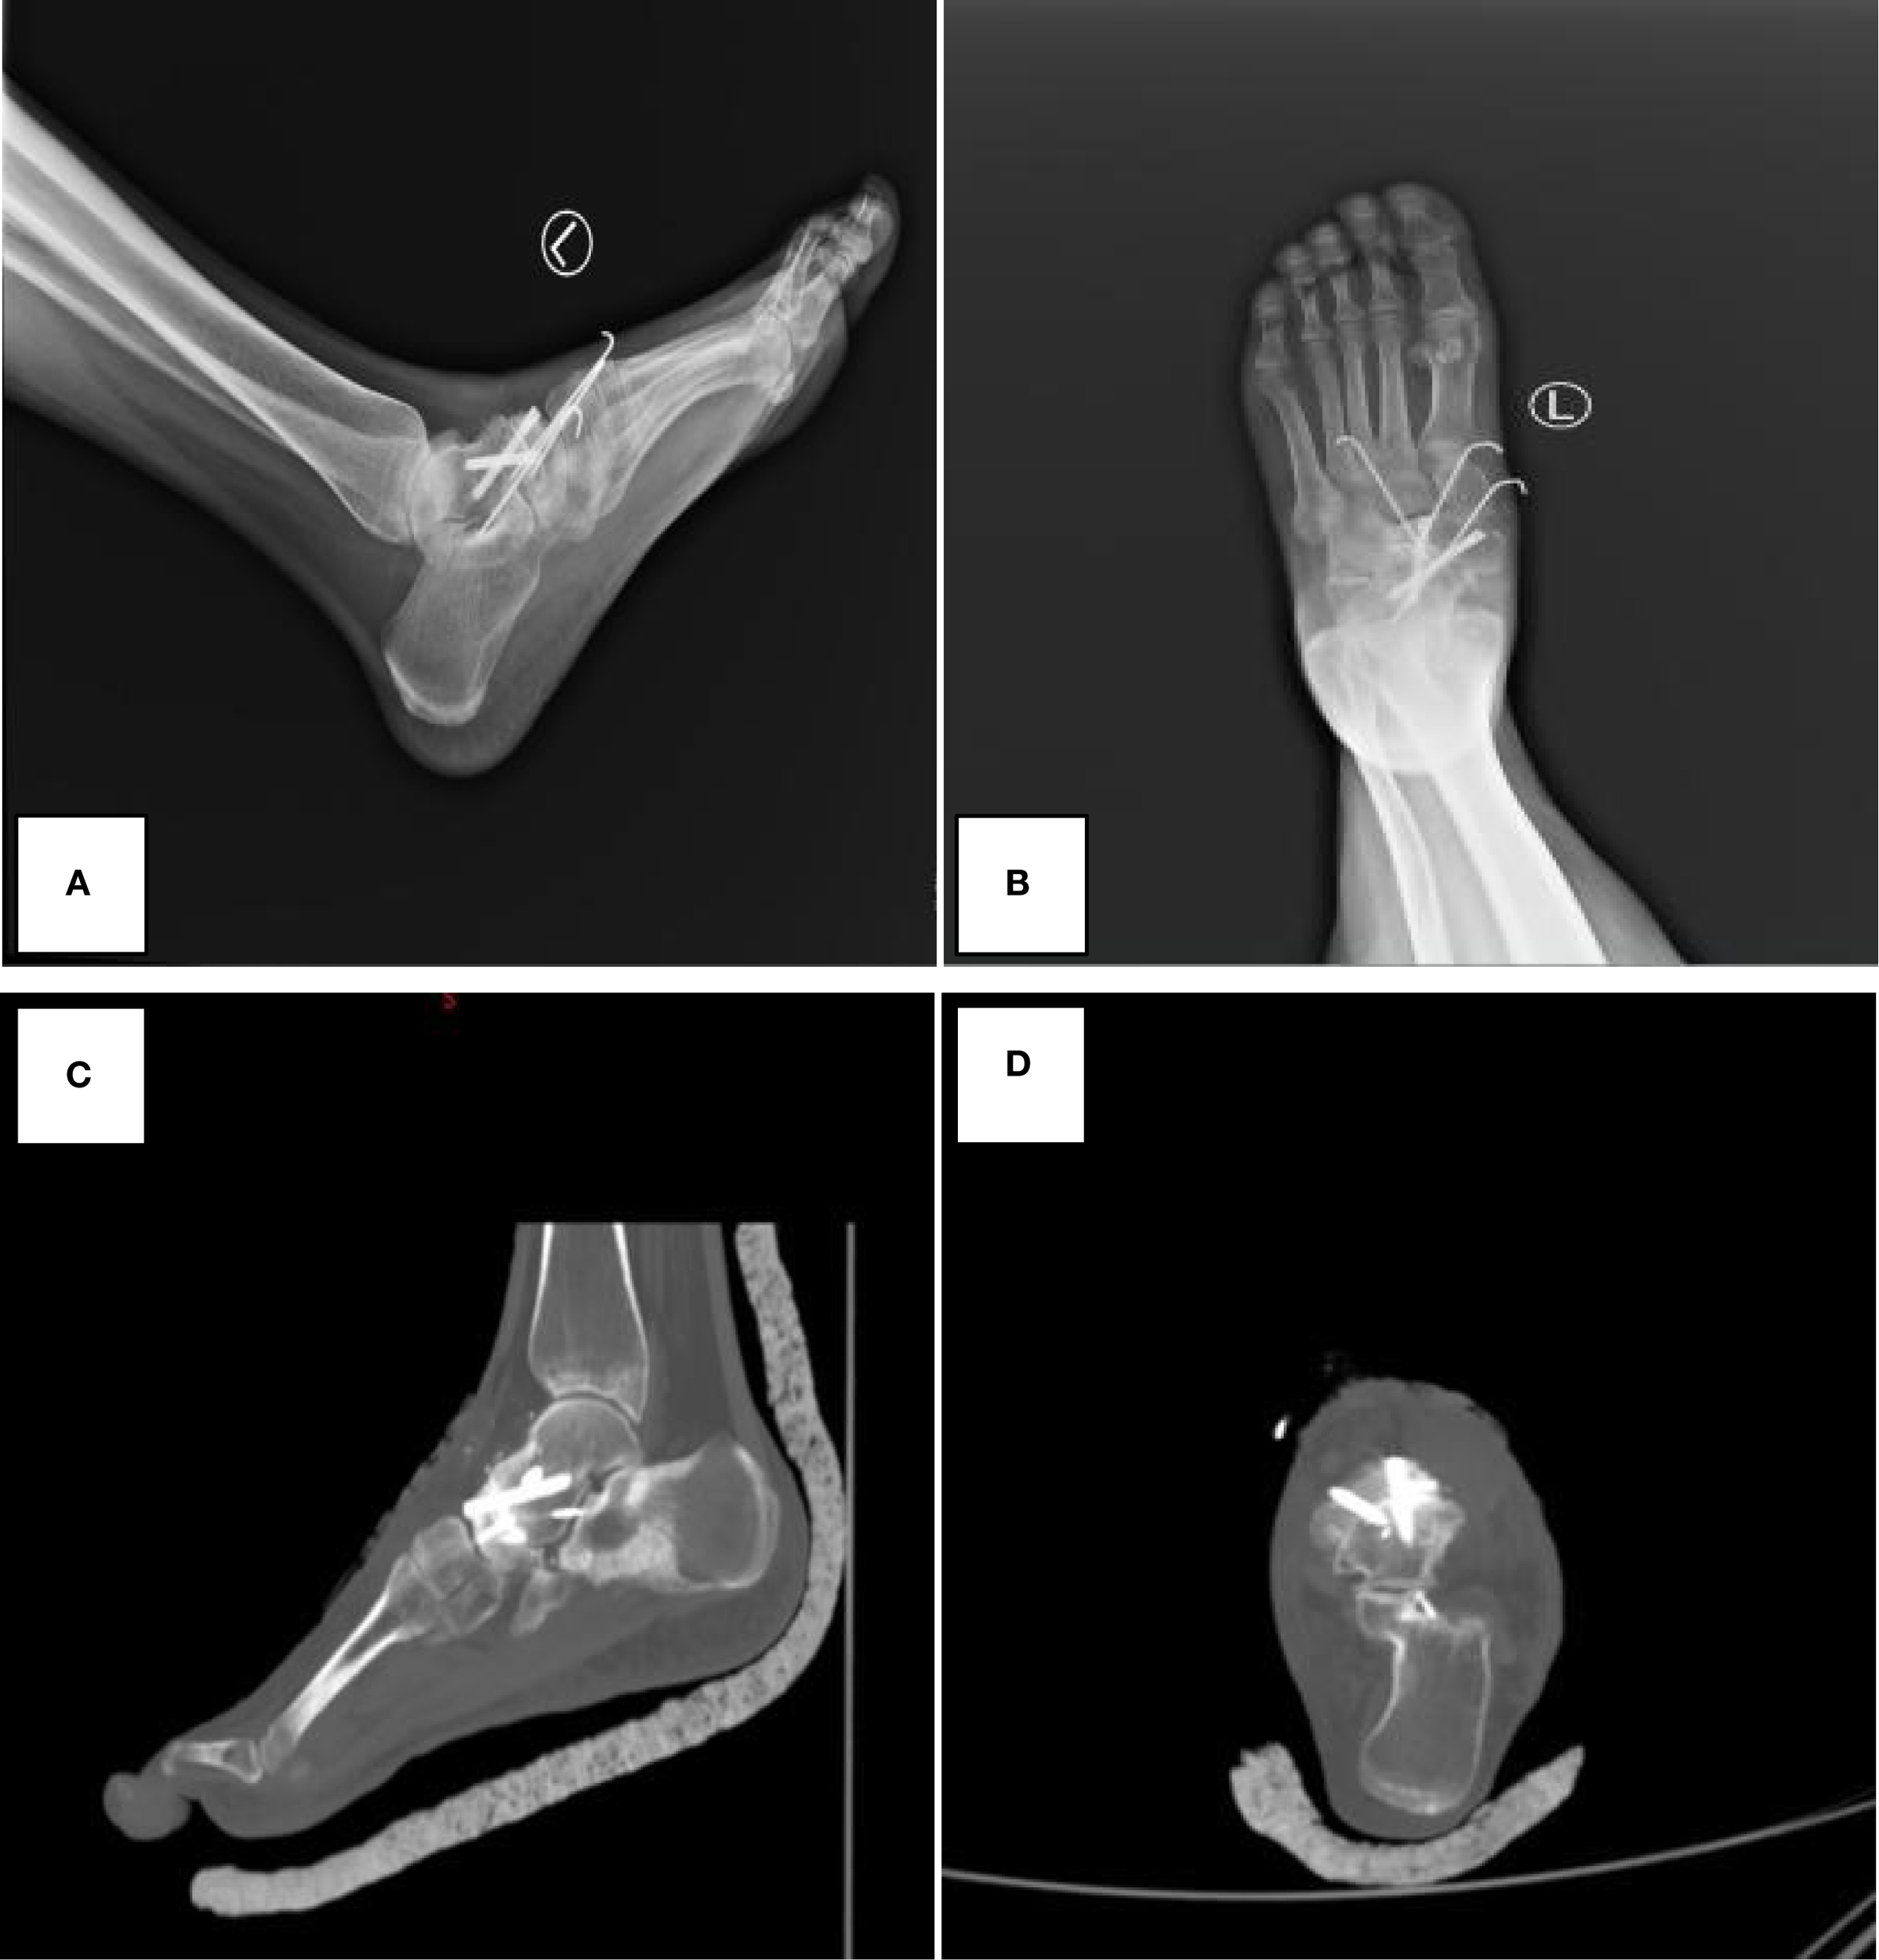

Figure 2

Postoperative imaging demonstrating successful talonavicular joint fusion with hardware in situ. (A, B) Postoperative X-ray images. (C, D) Postoperative CT images. The images demonstrate good alignment of the talonavicular joint and internal fixation.